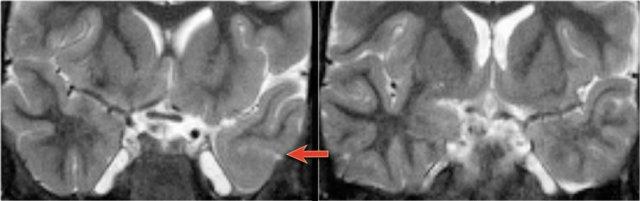

FLAIR axial, DWI axial và T2W coronal cho thấy hải mã tăng tín hiệu với sừng thái dương của não thất bên bị thu hẹp nhẹ, phù hợp với phù nề hải mã.

DWI cho thấy hạn chế khuếch tán do phù nề độc tế bào trong giai đoạn cấp tính của trạng thái động kinh liên tục.

T2W axial cho thấy hải mã tăng tín hiệu nhưng phì đại với hình ảnh dạng bong bóng.

Đây là hình ảnh điển hình của DNET hay u thần kinh biểu mô loạn sản phôi thai, sẽ được thảo luận chi tiết ở phần tiếp theo.

T1W coronal sau tiêm thuốc tương phản từ cho thấy hải mã phì đại không ngấm thuốc tương phản từ.